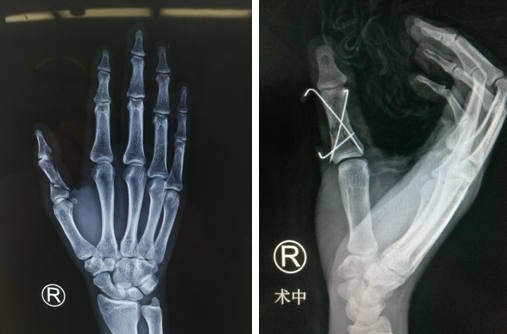

患者家属把患者送至我院后,急诊科的医护人员为患者积极完善各项术前检查,将右手掌及拇指伤口包扎止血,并行右手X线检查,结果显示右拇指近节指骨粉碎性骨折。

急诊科的医护人员立即联系了急诊值班的手外三科的吴尧医生,吴尧医生接到通知后为患者安排了紧急手术。手术中发现患者右手掌伤口内韧带、肌腱损伤,桡骨轻微骨折,右拇指近节粉碎性骨折,经过2个小时,手术顺利完成,复位情况很好。